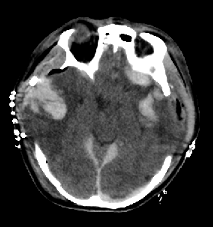

"SQUEEZE MY HAND!" Verbal commands like this are issued daily to traumatic brain injury patients in ICUs around the world. Persistent absence of command following is felt to be a poor prognostic sign. Is it? We share new results in JAMA Network Open 1/4

Verbal commands like this are issued daily to traumatic brain injury patients in ICUs around the world.

Persistent absence of command following is felt to be a poor prognostic sign. Is it?

After a severe TBI, the risk of unfavorable 1-yr outcome increases by 1% with each additional day without command-following . This was observed in two independent studies, together including > 9,000 patients. We dub this the "1% rule". manuscript: tinyurl.com/yvs9s7xu 2/4

After a severe TBI, the risk of unfavorable 1-yr outcome increases by 1% with each additional day without command-following .

This was observed in two independent studies, together including &gt; 9,000 patients.

Time to command-following is generally not a very good predictor, only weakly discriminating between 1-yr outcomes (AUC 0.6). A 90% likelihood of unfavorable outcome is reached only after MORE THAN 40 DAYS without command-following-- an extremely rare occurrence. 3/4

Time to command-following is generally not a very good predictor, only weakly discriminating between 1-yr outcomes (AUC 0.6).

A 90% likelihood of unfavorable outcome is reached only after MORE THAN 40 DAYS without command-following-- an extremely rare occurrence.